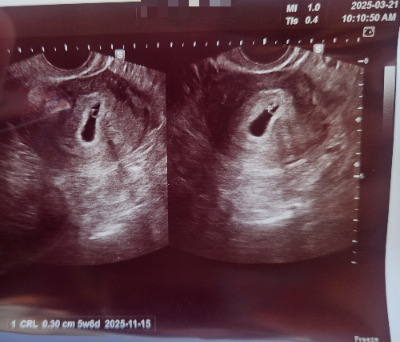

다행히 초음파는 멀쩡했다!

지난 진료 때는 못 봤던 난황이 점처럼 보였다. 일단 초음파 소견으론 자궁 내에 피고임도 없고 괜찮아 보인다고 했다. 내가 동동거리며 걱정을 계속 늘어놓으니 선생님이 유산방지제를 권했다. 할 수 있는 최선을 다하고 싶었다. 호르몬 조절로 자궁벽을 두텁게 유지해 주는 약이라고 했다. 당장 처방을 받아 그날 저녁부터 유산방지제를 먹기 시작했다. 아기가 거품처럼 사라질까 봐 너무 무서웠다.

난황이 선명해져서 좋다고 생각했는데 아니었다.

마지막 초음파로부터 3일이나 지났는데 아기는 고작 1mm 남짓 자랐다고 했다. 정상 아기라면 하루에 1mm씩은 자라야 한다고 했다. 아기가 너무 안 크고 있었다. 3일 전 진료에 5주 4일이었는데 아직도 5주 6일이었다. 아기는 0.09mm밖에 자라지 않았다. 아직 심장소리도 잡히지 않았다. 선생님 표정이 어두워졌다. 걱정스러운 목소리로 말씀하셨다.

"나흘 뒤 다시 와서 초음파를 다시 보셔야 할 것 같아요. 그때도 만약 심장소리가 없거나, 아기가 너무 작으면 유산으로 보셔야 할 것 같습니다."